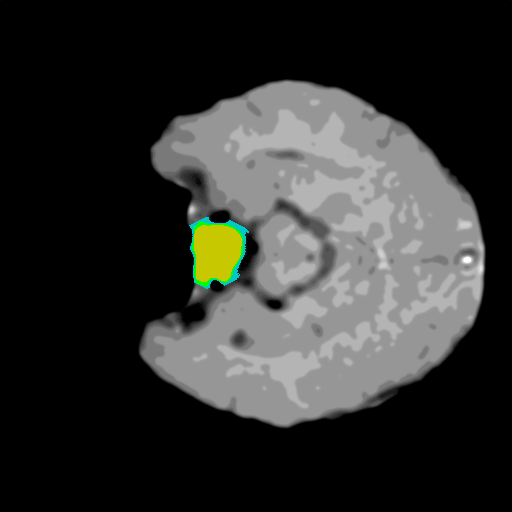

Extensive experiments have been performed in the current setup, and experimental outcomes are reported with the demonstration of numerical and statistical analyses using the proposed QFS-Net, QIS-Net [39], convolutional U-Net [18] and Residual U-Net (URes-Net) architectures [20]. The human expert segmented skull-tripped contrast enhanced DSC brain MR input image slices of size and ROIs are provided in Figure 5 as samples. The demonstration of QFS-Net segmented images followed by the essential post-processed outcome on the slice no. for class level with four distinct activation schemes () are shown in Figure 6. It is evident from the experimental data provided in Table LABEL:tab1 that the proposed QFS-Net performs optimally for the -connected quantum fuzzy pixel information heterogeneity assisted activation () with and gray scale set in comparison with other thresholding schemes and gray scale sets under the four evaluation parameters () [44]. The segmented tumors obtained using the proposed self-supervised procedure under class transition levels with four different thresholding schemes , , and are demonstrated in Figures 7- 8 for the class boundary sets and [39], respectively. The segmented images using the remaining two class boundary sets ( and ) [39] are provided in the supplementary materials section. The segmented ROIs describing the whole tumor region after the masking procedure using QIS-Net, U-Net and URes-Net are also reported in Figure 9.